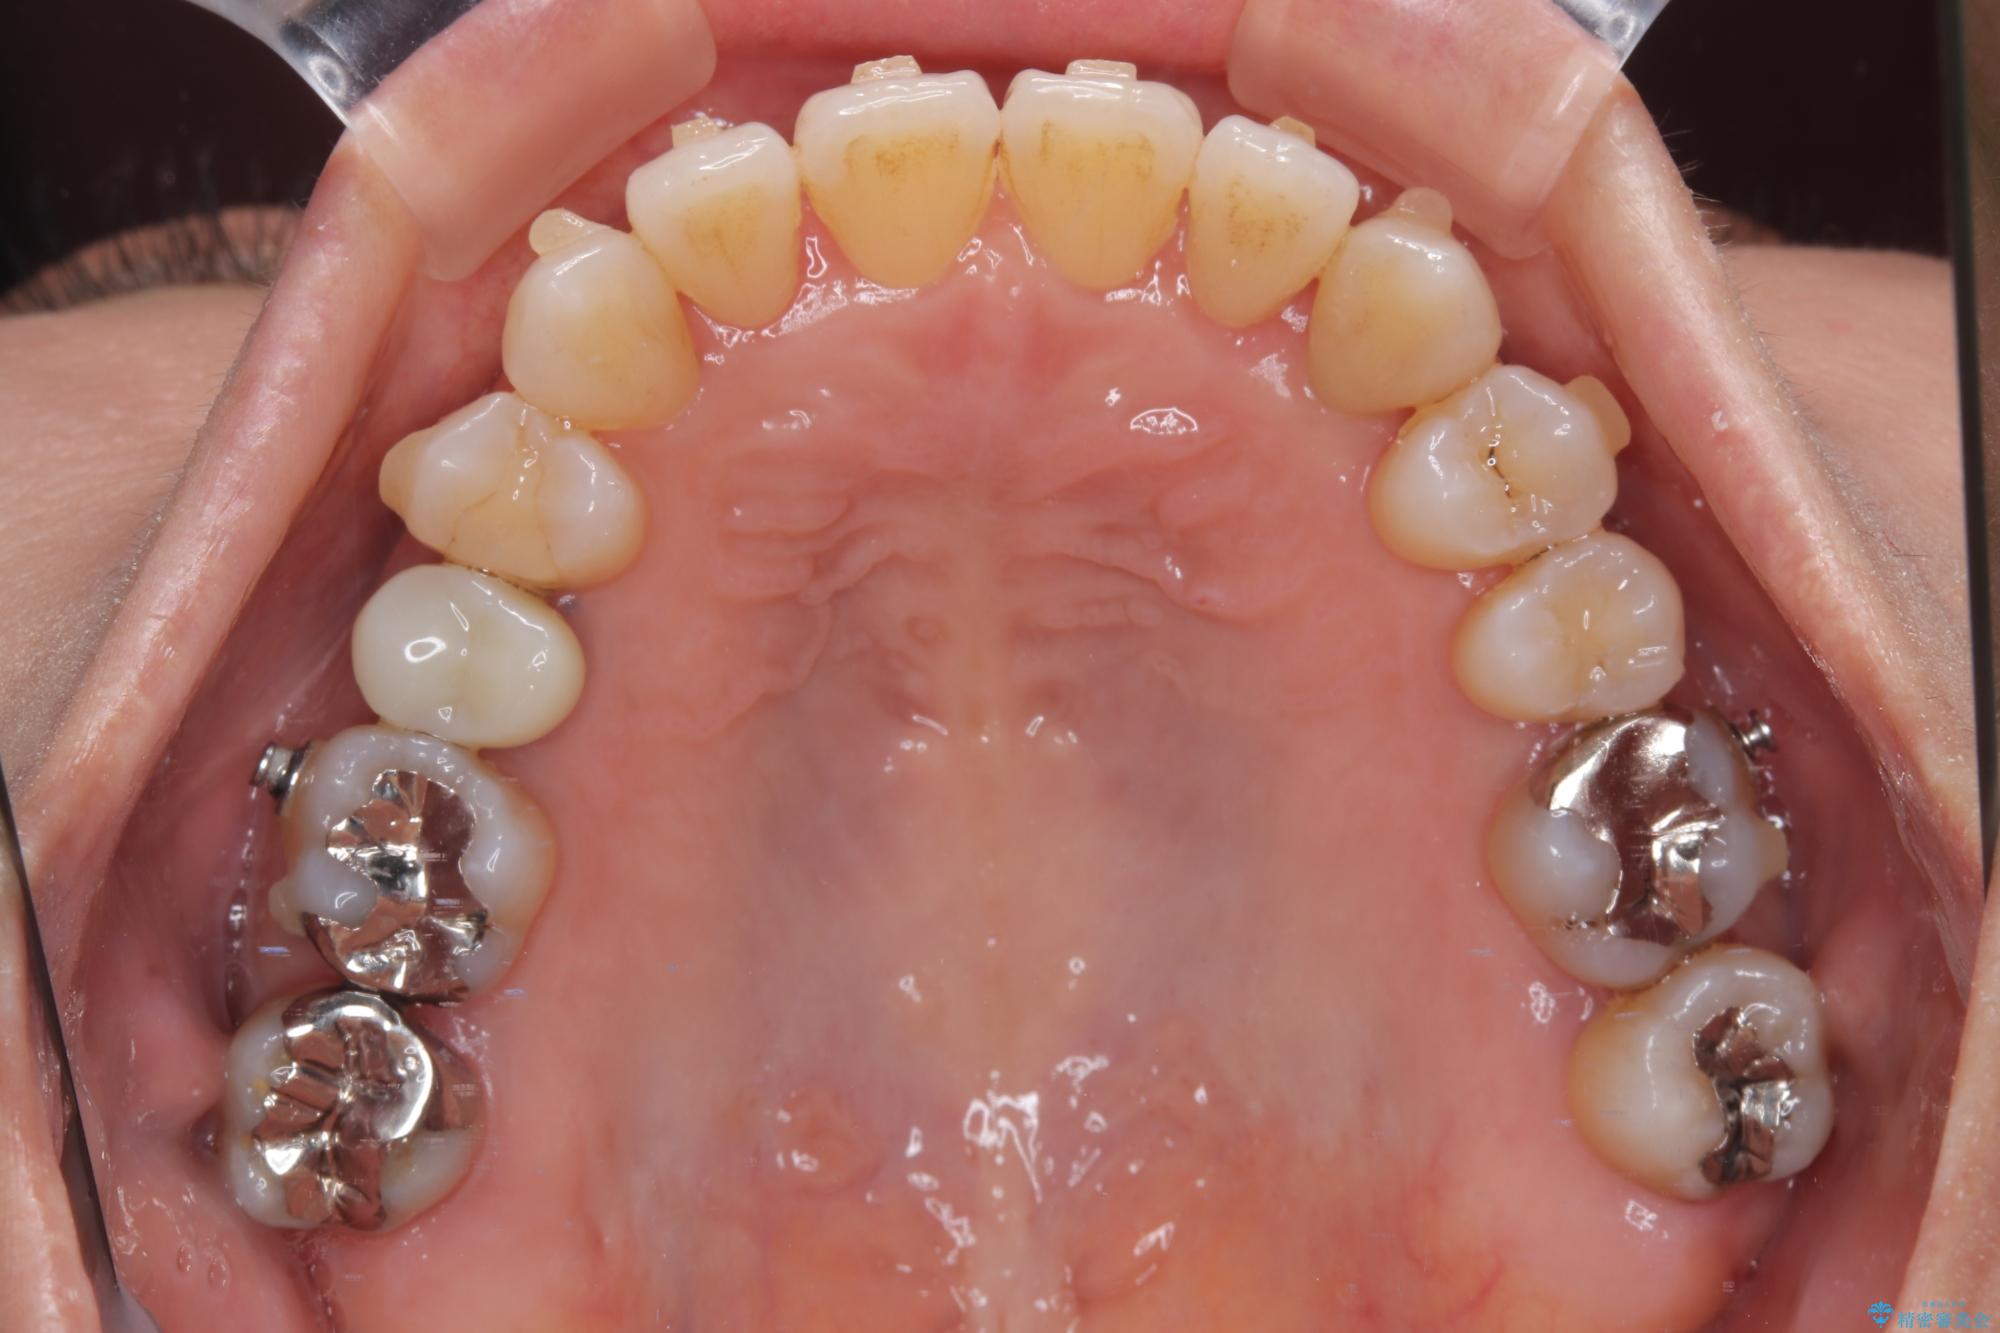

受け口と八重歯を改善 インビザライン矯正治療

- 前歯のデコボコや八重歯を治したいとのことで来院された患者様です。

受け口傾向の骨格であり、前歯はクロスバイトまたは切端咬合となっており、下顎を中心に歯列全体の後方移動を行い、IPR(歯と歯の間を削る)によってデコボコが解消するように設計し、インビザラインにより治療を行うこととしました。

受け口傾向のインビザライン矯正は比較的治療を行いやすいため、きれいに仕上げることができました。舌の突出癖が顕著であったため、改善のためのトレーニングをしっかりと行っていただきました。